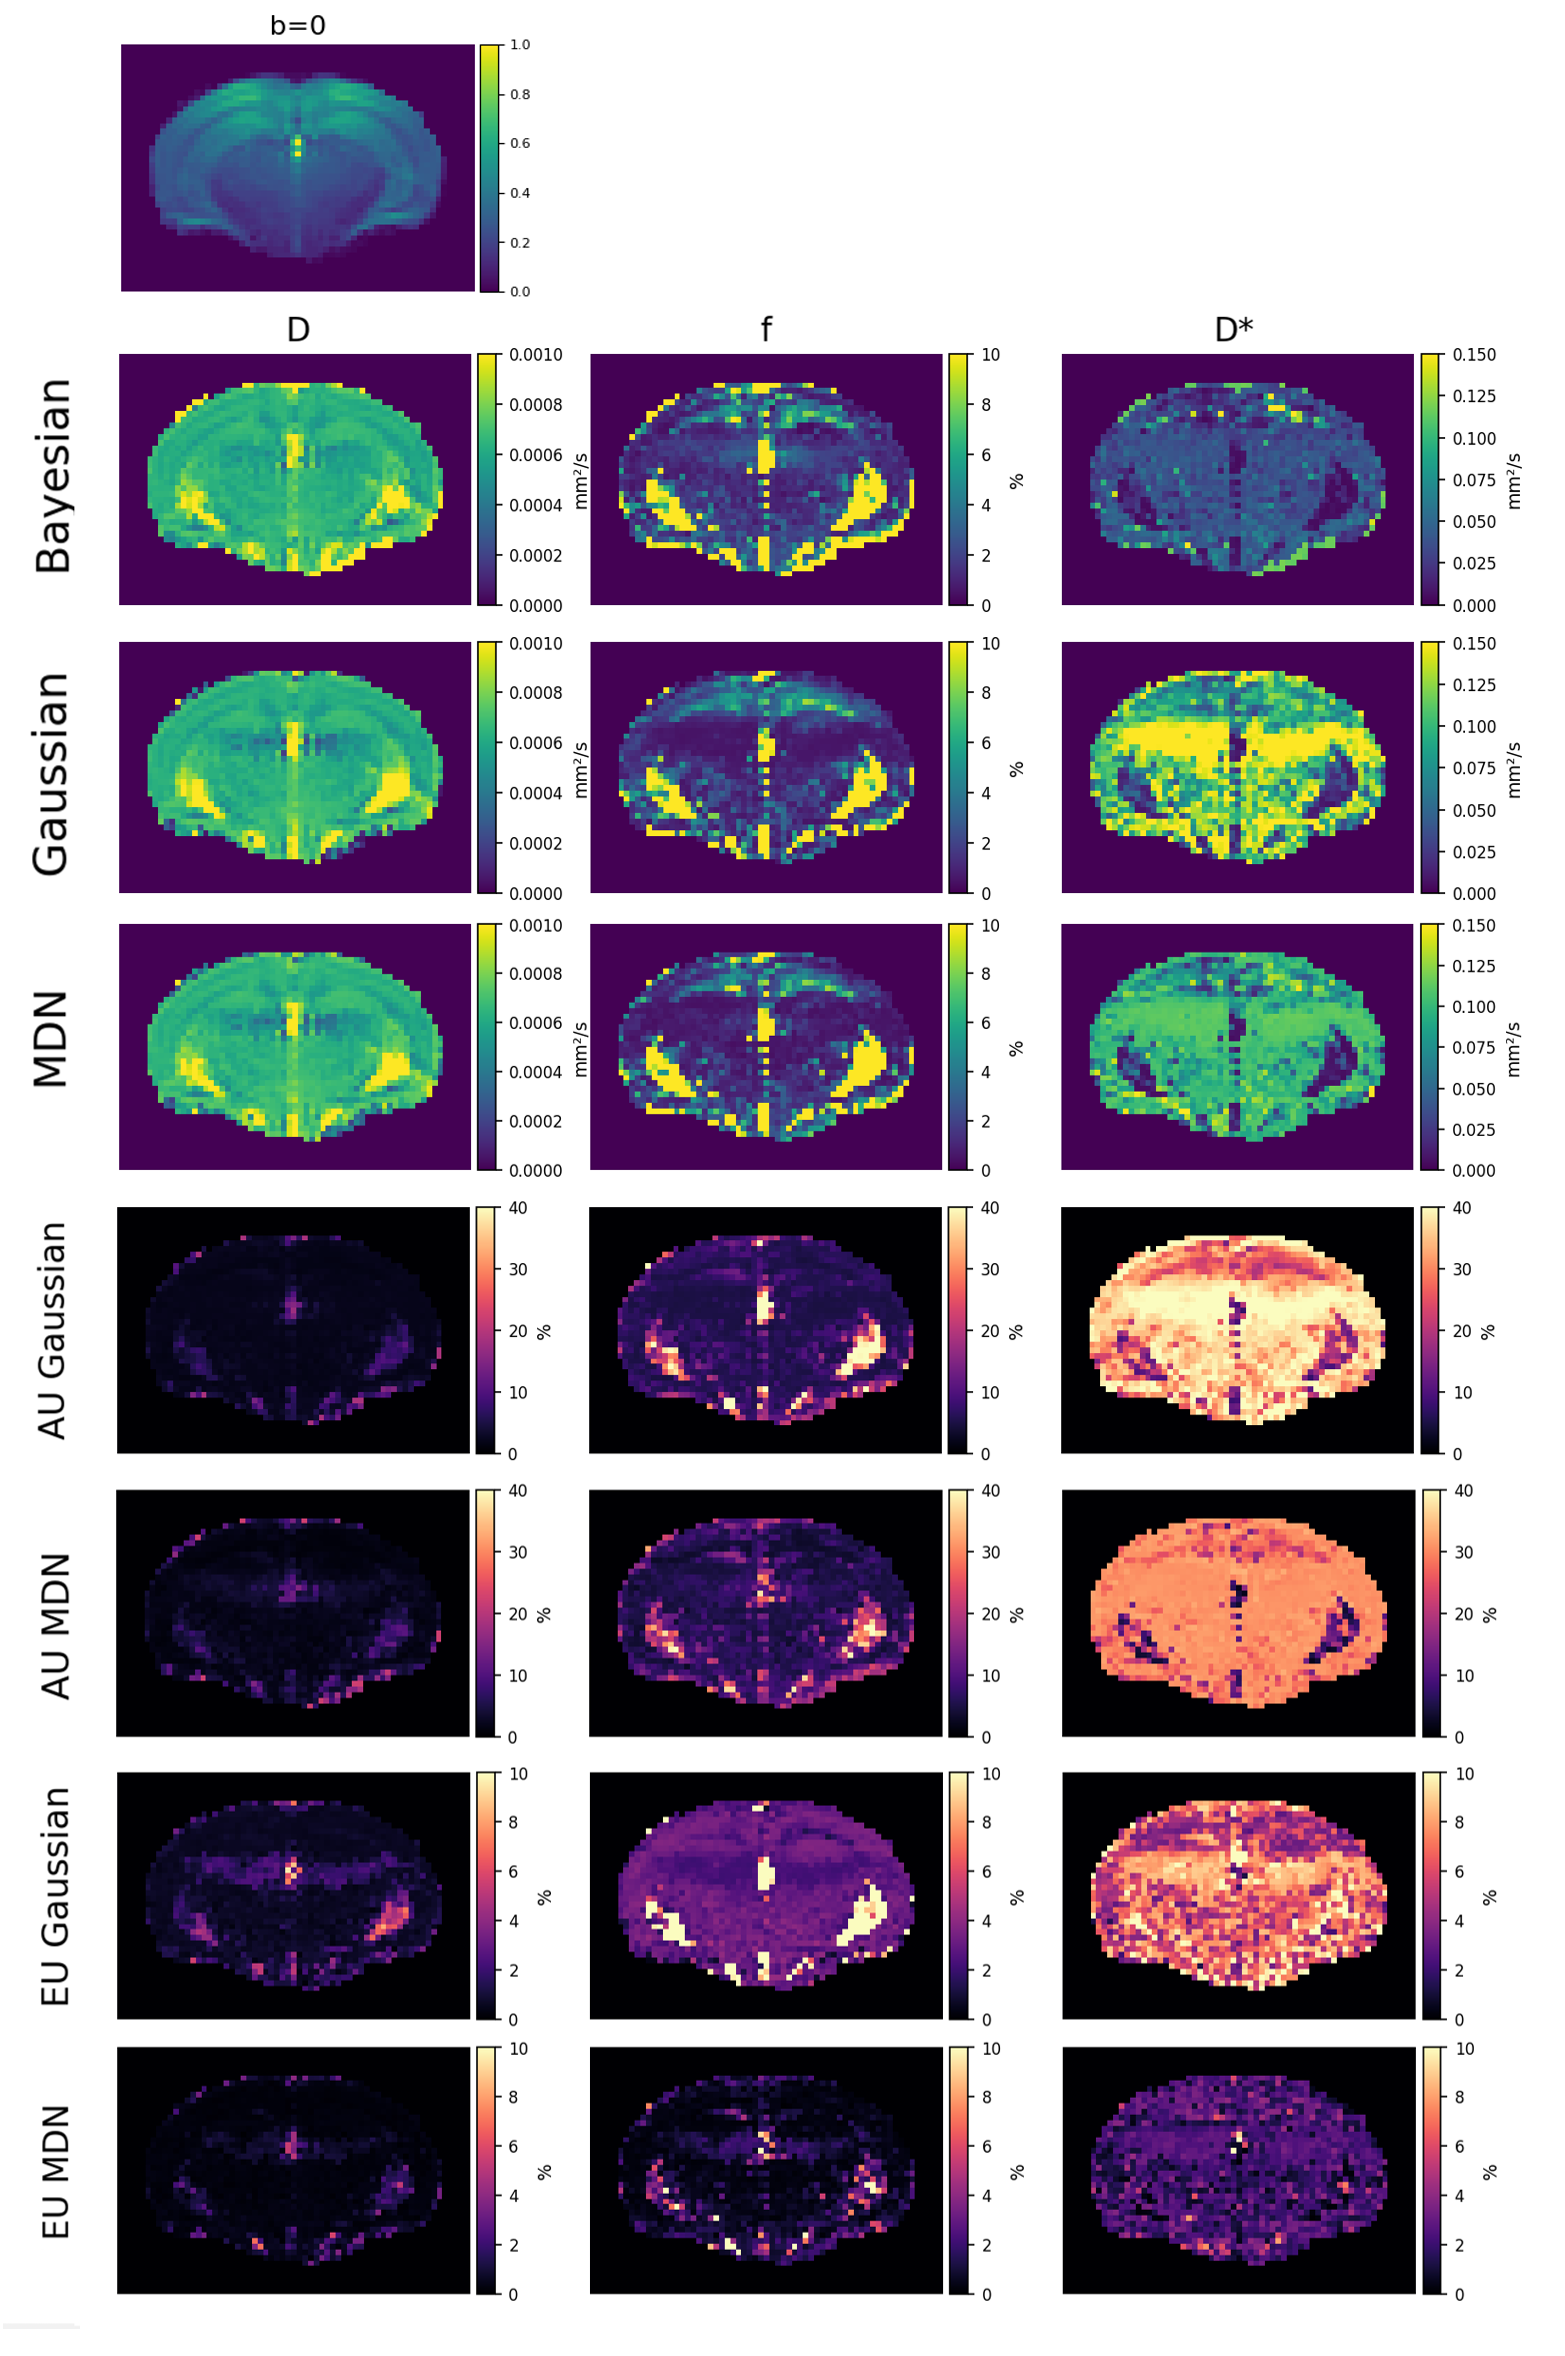

3.2 In Vivo Data

3.2.1 IVIM Parameters Estimation

An example of predictions on the in vivo brain mouse is reported in Figure 5. Table 3 presents the median and MAD of IVIM parameter estimates across the four different models. All methods produced similar estimates for ( mm2/s). There was slightly variability in , where the Bayesian model yielded the lowest values (), while Gaussian and MLP estimated higher values (). NNs also reported higher pseudo-diffusion values ( mm2/s) compared to the Bayesian model ( mm2/s) .

Table 4 reports the RCV in brain ROIs. In this case, all models achieved low RCV for (), while variability in is the highest for Bayesian () and lowest for MLP (). MDN attained the best value for (), compared to Bayesian ().

4.2 In vivo data

Since ground truth IVIM parameters are not available in vivo, the evaluation focused on the median values and the RCV within manually delineated ”homogeneous” ROIs. Among the probabilistic approaches, the MDN achieved the lowest RCV for the parameter in the in vivo dataset (16.0%). The greater homogeneity in the MDN’s estimation of is also evident in Figure 5, where the Gaussian model exhibits regions with values exceeding 0.15 mm2/s, which are patterns not observed in the Bayesian or MDN estimations. For , the Gaussian model achieved a lower RCV (42.5%) compared to the MDN (53.5%).

While EU was generally lower on average compared to AU, as shown in Table 2, neglecting this component can lead to an underestimation of the total predictive uncertainty for specific regions. This can be seen in Figure 5. In the maps, elevated values are observed in the ventricular regions, which are filled with cerebrospinal fluid and are not expected to exhibit perfusion. In such regions, the IVIM signal primarily reflects diffusion, and due to low , the contributions of diffusion and perfusion may become indistinguishable 30. These erroneous estimations are flagged by high AU values and, to a lesser extent, elevated local EU, which reinforces the importance of accounting for both uncertainty types when interpreting model outputs in complex anatomical regions.